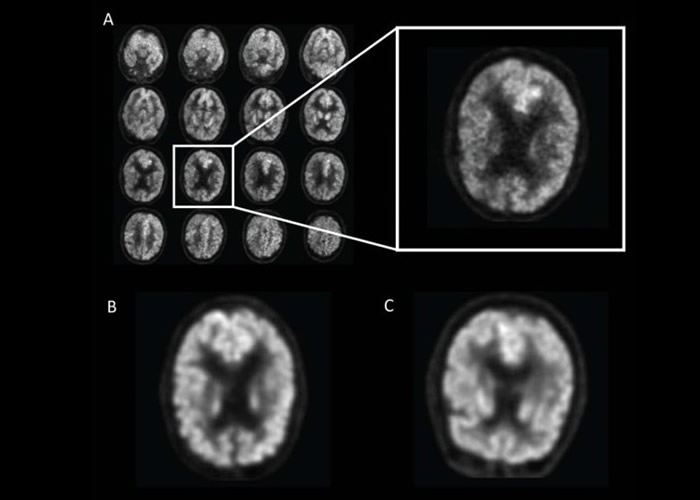

加州大学三藩市分校放射与生物医学影像学系的研究人员,从一个早老性痴呆症病人数据库,取得1002名病人共逾2100正电子扫描(PET)影像,并让AI系统在其中90%影像中,学习使用PET技术,检测脑部代谢活动指标氟代脱氧葡萄糖(FDG)摄取量。研究人员之后让AI在其馀10%影像测试,让它从中学习深度运算。

研究人员再让AI系统检测另外40张从未检测过的病人脑部扫描影像,结果系统能检测到病人在最终确诊之前平均逾6年,已经患有早老性痴呆症,准绳度达百分百。报告共同撰写人孙在镐(Jae Ho Sohn,音译)表示,及早发现脑退化征状有助提供更适切的治疗,以及减慢、甚至是停止病情恶化。